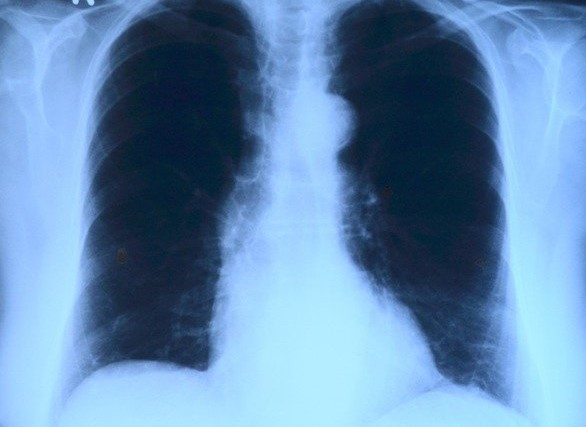

Симптом COVID может быть признаком рака лёгких

Один из основных симптомов коронавируса — постоянный кашель — можно перепутать с признаком другого опасного заболевания — рака лёгких. Однако у последнего немного другая клиническая картина. Для рака характерны также кровохарканье, потеря веса и аппетита, а также одышка.

Рак лёгкого — это злокачественное новообразование в органе дыхания, появившееся из эпителиальной ткани бронхов различного калибра.